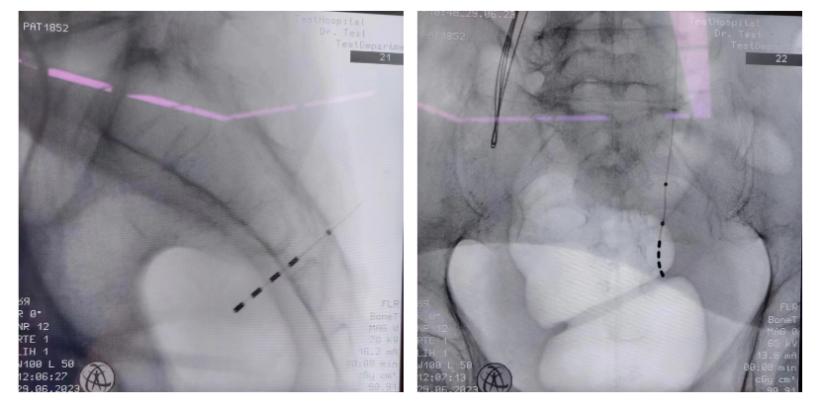

查看详情2023年6月29日,在华西医院泌尿外科沈宏教授、金涛教授的指导下,我院盆底疾病中心罗德毅教授与康悦教授联合成功开展了西部地区首例新型远程可程控、II期可充电式骶神经调控手术。确诊“脱髓...